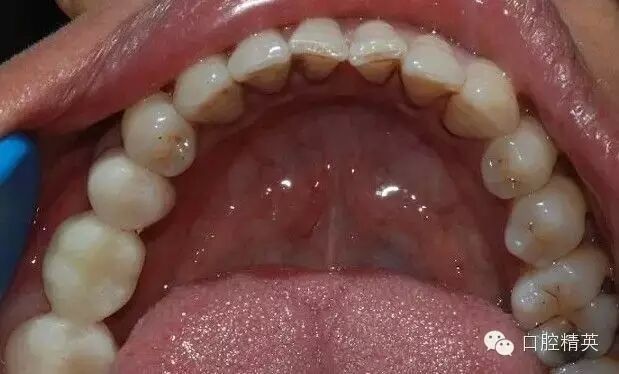

46缺失,不考慮種植牙,45、47做基牙,固定烤瓷橋修復(fù);這是口內(nèi)的情況